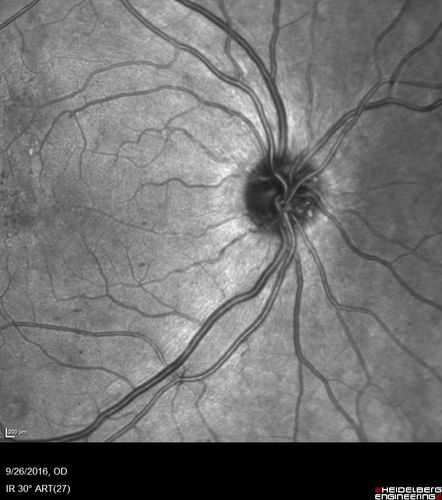

PDR NVD left eye and NVE right eye

41 year old diabetic woman with PDR in both eyes. High risk in the left eye. She had PRP, Avastin, and vitrectomy x 2 in the left eye with final vision of 20/25. The right eye had eventually PRP laser

Proliferative Diabetic Retinopathy NVD left eye and NVE right eye - Ultrawide field FA